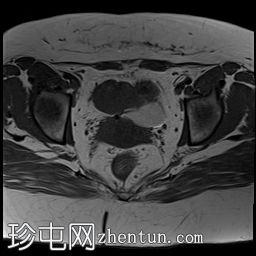

MRI

7.jpg

轴向

T1

子宫下段前壁变薄,存在约 5 毫米的小缺损/裂开,并从中突出一个大囊性病变/憩室,与子宫内膜腔相通。它在 T1WI 和 T2 WI 上显示高强度信号,在 T1FS 上没有信号下降,表示有出血信号。发现结果与先前子宫下段手术疤痕处的子宫龛裂开一致,憩室(峡部膨出)含有出血内容物。

子宫大小正常,子宫内膜厚度正常,无明确局灶性病变。

左卵巢囊性病变显示内部分隔,在 T1WI 和 T1FS WI 上呈现低到高混合信号,在 T2WI 上呈现高信号,提示左卵巢出血性囊肿/子宫内膜异位症。囊肿后内侧可见消失的卵巢组织和卵泡。

右卵巢增大(17 cc),显示多个小卵泡液体信号。